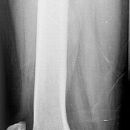

Oberschenkel seitlich

Patient in Seitenlage, aufzunehmendes Bein liegt mit der Außenseite auf, in der Hüfte möglichst gestreckt, im Knie leicht gebeugt, das andere Bein nach hinten gestreckt oder aufgestellt (etwas zurückziehen).

Senkrecht auf Oberschenkel- und Kassettenmitte, Kassettenrand siehe Oberschenkel a.p.

Bei fehlender Möglichkeit zur exakten Seitenlage, bei Frakturen oder Erguss – Aufnahme im horizontalen Strahlengang mit angestellter Kassette (siehe seitl. Knie).

Oberschenkel wird exakt lateral abgebildet, Hüftgelenk gut einsehbar, Schenkelhals stark verkürzt und durch den Trochanter major verdeckt. Distaler Oberschenkel mit guter Darstellung des Kniegelenkspalt.